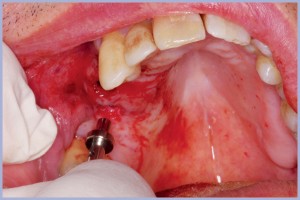

Si realizza la Dima Chirurgica e si programma l’intervento in sedazione cosciente perché il paziente è un soggetto ansioso, con la collaborazione della specialista in anestesia. La sedazione cosciente viene indotta con miscela di gas di protossido di azoto e ossigeno e benzodiazepina a emivita breve (Midazolam) in vena. Con questa tecnica il paziente mantiene i riflessi oro-faringei e risponde ai comandi a seconda dell’esigenza dell’operatore. Si esegue, comunque, l’anestesia locale per infiltrazione con articaina 1:100000, si inserisce la Dima Chirurgica e si esegue lembo mucoso con mucotomo circolare.

In seguito, si esegue la sequenza delle frese chirurgiche con stop e diametri e lunghezza pianificati con sistema Real Patient™ Guide System (3DIEMME® Srl, Cantù (Co)), si inseriscono gli impianti e i tappi di guarigione e si congeda il paziente senza aver eseguito il lembo chirurgico e punti di sutura (Figg. 1-38). I vantaggi della chirurgia guidata flapless sono un edema e dolore post- intervento minori, riduzione dei tempi di guarigione, assenza di riassorbimento osseo dopo esposizione con il lembo e minori disagi per il paziente (riduzione dei controlli, assenza di dieta liquida e assenza di rimozione dei punti di sutura) e per l’operatore (sicuramente riduzione dello stress). Ovviamente non sempre si può eseguire un intervento di chirurgia guidata a cielo coperto; è, infatti, indispensabile avere a disposizione un discreto osso in termini di qualità e quantità . Con questi presupposti il sistema assicura un’ottima predicibilità e la possibilità di effettuare anche un carico immediato con protesi provvisoria.

- Figg. 31-35 – Posizionamento guidato degli impianti